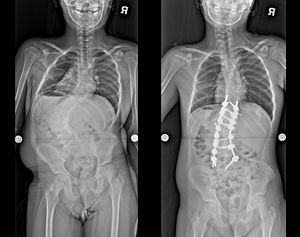

病例二 |

| 術前 |

術後 |

| 正向X光片 |

| 側向X光片 |